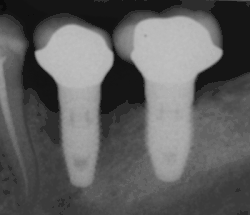

Failure to integrate

An implant is tested between 8 and 24 weeks to determine if it is integrated. There is significant variation in the criteria used to determine implant success, the most commonly cited criteria at the implant level are the absence of pain, mobility, infection, gingival bleeding, radiographic lucency or peri-implant bone loss greater than 1.5 mm.[92]

Dental implant success is related to operator skill,[93] quality and quantity of the bone available at the site,[2] and the patient's oral hygiene, but the most important factor is primary implant stability.[94] While there is significant variation in the rate that implants fail to integrate (due to individual risk factors), the approximate values are 1 to 6 percent[42]: 68 [75]